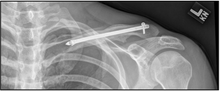

| X-ray of a left clavicle fracture | |

A discontinuity in the bone shape often results from a clavicular fracture, visible through the skin, if not treated with surgery. Surgical procedure often call for open reduction internal [plate] fixation where an anatomically shaped titanium or steel plate is affixed along the superior aspect of the bone by several screws. In some cases, the plate may be removed after healing, but this is very rarely required (based on nerve interaction or tissue aggravation), and typically considered an elective procedure. Alternatively, intramedullary fixation devices (within the medullary canal) can be implanted to support the fracture during healing. These devices are implanted within the clavicle's canal to support the bone from the inside. Typical surgical complications are infection, neurological symptoms distal the incision (sometimes to the extremity), and nonunion.